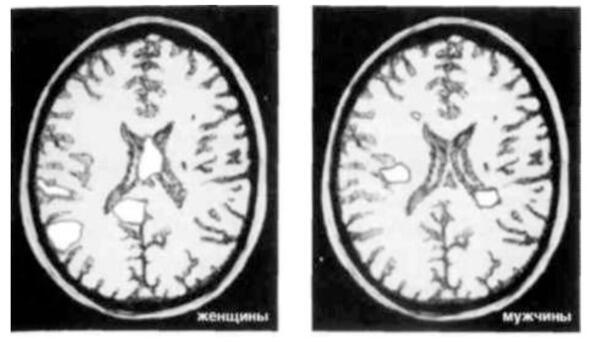

На снимках  результаты исследования, проведенного доктором Брауном. Показаны сканы мозга мужчин и женщин, которые смотрят на фотографии людей, в которых они страстно влюблены. На них хорошо видно, что у мужчин и женщин активизируются разные участки мозга.

На Рис.1 видно, что у мужчин светлых участков меньше, чем у женщин, но если смотреть на снимки в цвете, то заметно, что активизированные участки у мужчин более интенсивно окрашены.

Рис.1

Фишер и Браун, вместе и по отдельности, проанализировали результаты сканирования мозга более 3000 «безумно влюбленных» студентов, полученные в тот момент, когда им показывали фотографии любимых. Ученые обнаружили, что у женщин, принимавших участие в исследовании, проявлялась повышенная активность базальных ядер  области мозга, связанной с памятью, эмоциями, вниманием, «центром удовольствий», а также участвующей в формировании ментальных образов и воспоминаний. Эта часть мозга отвечает за подсознание и первобытные инстинкты, она гораздо сильнее рациональной, мыслящей части  коры. Вот почему влюбленные ведут себя иррационально.

Мужчины, участвовавшие в исследовании, демонстрировали повышенную активность участка коры, отвечающего за визуализацию, и зон, связанных с обработкой зрительных образов, а также области, отвечающей за сексуальное возбуждение.